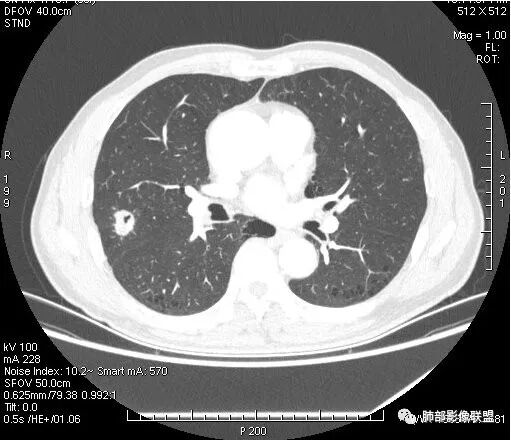

右肺上叶后段占位病灶,病灶不规则,周围胸膜线性牵拉,病灶部分周围有晕,病灶内见不规则空洞,未见明显引流支气管,长毛刺,多分叶、肿块边缘部分L型,可见血管直接供养。增强见点状坏死、病灶内血管。综上考虑恶性可能性大,鉴别隐球菌。

右上叶结节,轻分叶,结节有长短不一毛刺,结节周围GGO边界清,有血管集束征,肺窗结节周围似可见卫星灶,可见鬼脸征,良恶性征象都有,但GGO边界清,浸润性腺癌耍考虑,临床症状轻微,体捡发现,似可见卫星灶和鬼脸征,炎性肉芽肿TB或隐球菌要鉴别。

我们从外朝内,肺气肿背景

有毛刺吗?长?粗短?胸膜牵拉?

细毛刺,

有,长短都有,短的为主

细毛刺,胸膜牵拉

有分叶吗?

边缘是不是有些地方膨隆?

有卫星灶

这个病例确实有很多隐球菌的特点,包括周围的卫星灶、周围的毛刺,它没有粗短的毛刺,它是稍长一点、柔弱一点的。我是觉得这个符合脐凹征,所以我觉得恶性不能排除,结果错了,是炎性。

这个大部分边缘稍微偏平直一点,血管走行非常自然,包括里面的空泡征样的,影子很干净,边界很光滑,都是些炎性特点。

2.病灶有浅切迹,没有深分叶,毛刺大多细长且柔软。

3.可见棘状突起及胸膜牵拉,但未见胸膜凹陷。

6.灶周见小结节影(卫星灶),边界不甚清晰。